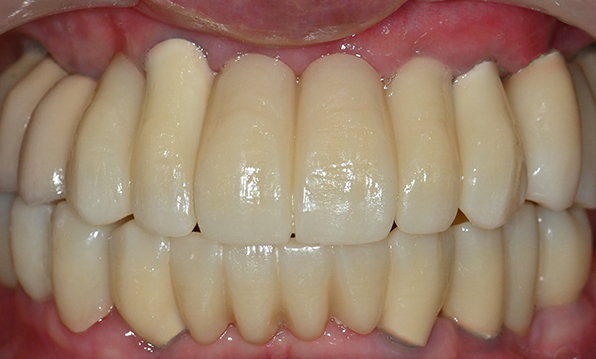

Case 02

Before After